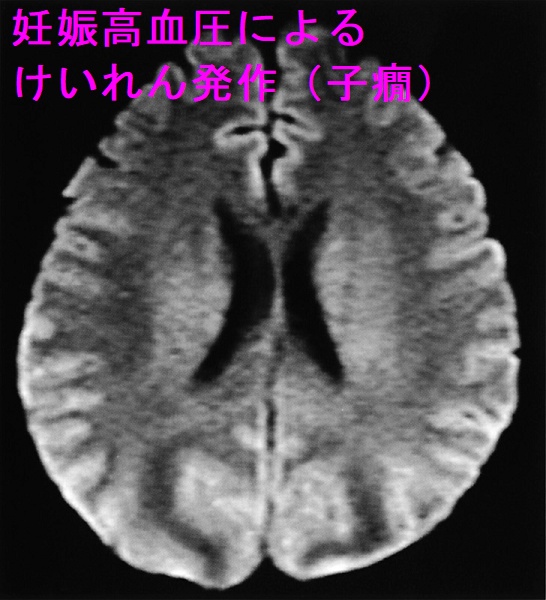

- 母体は妊娠高血圧、蛋白尿、子癇前症→けいれん発作(子癇)、脳出血、肝障害、腎障害、HELLP 症候群(ヘルプ症候群)、急性妊娠脂肪肝

重度の妊娠高血圧腎症(血圧160 mmHg/110 mmHg以上かつ蛋白2+など)では子癇予防のため、硫酸マグネシウム投与が推奨されます。